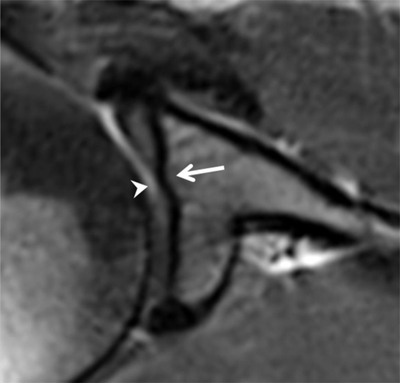

Figure 24

Pulley system. Axial fat-saturated T1-weighted MR arthrographic section at the level of the bicipital groove shows the biceps pulley (large arrow), formed by the fusion of the coracohumeral ligament, the superior glenohumeral ligament (thin arrow) and the transverse humeral ligament. The long head of the biceps tendon is pointed out by an arrowhead.